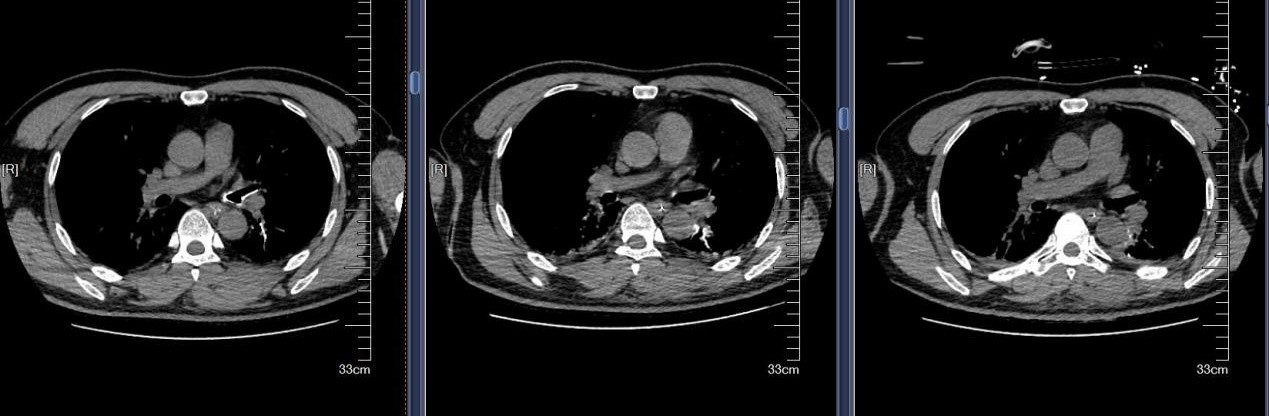

近日,苏州大学附属第四医院成功救治一例极其罕见的支气管异物危机案例。患者是一名48岁男性,因全身被水泥覆盖,伴有意识不清、呼吸困难等危急症状。紧急送医至我院后,CT检查发现其气管和双侧主支气管内充满大量高密度泥沙状异物,同时伴有多发肋骨骨折及腰椎骨折等严重外伤。面对如此复杂的病情,苏大附四院呼吸与危重症医学科蒋军红主任率领团队迅速制定了精准救治方案,成功挽救患者生命。

水泥作为化学性异物,除了造成机械性呼吸道阻塞,还会引发严重的化学性肺炎和呼吸衰竭。患者到院时已出现意识不清、呼吸困难等危重症状,气道清理成为抢救的首要目标。我院蒋军红主任凭借丰富的临床经验和技术优势,带领团队展开了一场与时间竞速的生命营救。